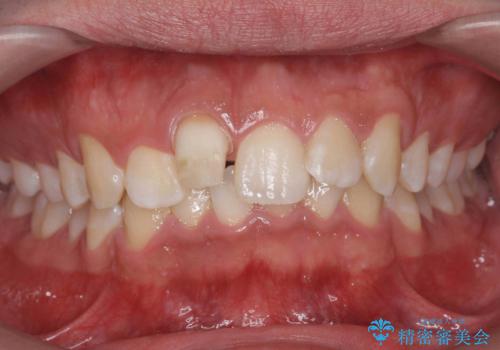

変色した前歯 根の治療とセラミックで白い歯に

- 前歯の変色を主訴に来院。

神経が死んでいたため、神経の治療を行いました。

また、全体的に歯石がついており、歯ぐきから出血しやすい状態であったため、TBI(歯磨き練習)を行い、歯茎の炎症をしっかり収めてから治療しました。

今後矯正治療をするかもしれない(未定)とのことでした。

その際、支障がでないように、患者様と相談し、他の歯を削って並びを整えるようなことはせず、前歯の角度はそれなりにそろえる形にしました。

神経が死んでしまった歯は時間がたつと変色してきてしまいます、セラミックでかぶせると色を改善することが可能です。